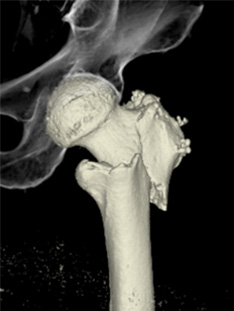

CT検査室

体の周囲360度からX線を照射し、体内を透過したX線量を解析し、画像にします。輪切りの画像だけでなく任意の断面の画像を作成でき、血管や骨などを立体的(3D)に表示することができます。 撮影時間を短縮、広範囲を撮影でき、息止めがある検査でも数秒と負担なく検査を受けられます。また体の大きさ、形に合わせてX線の量が自動で調整されるため被ばくを低減することができます。